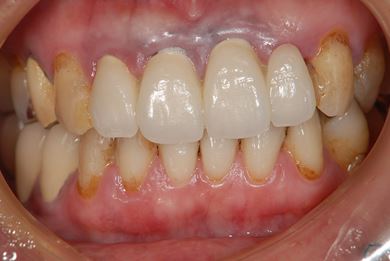

インプラント治療+セラミック治療

| 治療方針 | インプラント・セラミック治療にて、機能的・審美的回復を行う。 | ||||||||||||||||||||||||||||||||

| 治療内容 | インプラント3本、ジルコニアフレームオールセラミッククラウン7本(ジルコニア用土台1本)、メタルボンドセラミッククラウン3本(メタルボンド用土台3本)、ハイブリッドセラミッククラウン3本、ハイブリッドセラミックインレー3本 | ||||||||||||||||||||||||||||||||